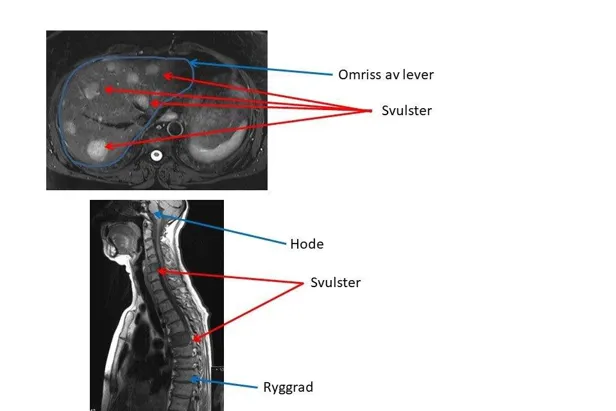

Ved hjelp av disse undersøkelsene kan en svulst påvises. Noen ganger kan imidlertid svulstene være såpass små, eller ligge slik til, at de ikke identifiseres på røntgenundersøkelsene. Ofte må det brukes kontrast på CT undersøkelsene for at svulsten skal oppdages (intravenøs kontrast i arteriell og portovenøs fase).

Likeledes vil MR-oppdage flere svulster og gi bedre tolkningsmuligheter av sykelige forandringer ved bruk av kontrast. MR er bedre til å påvise svulster i skjelettet enn CT.